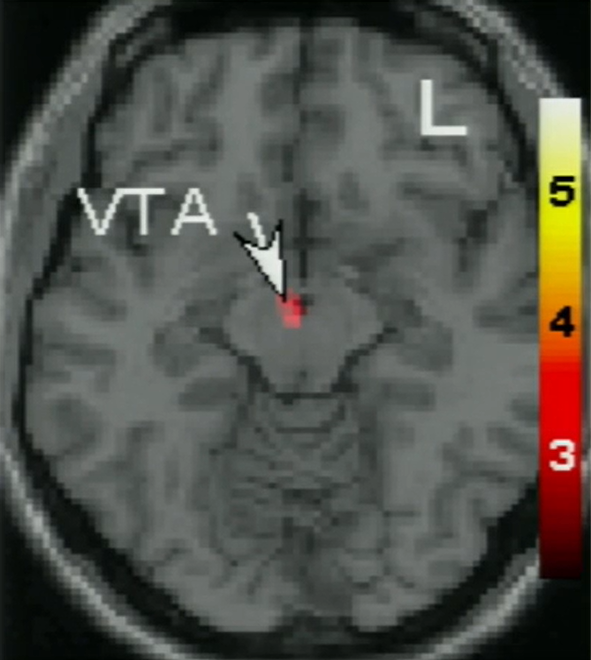

그런데, 이 3년이라는 수치는 놀랍게도 뇌과학자들의 연구 결과와 정확히 일치한다. 사랑에 빠진 인간의 뇌에서 가장 눈에 띄는 부위는 바로 VTA(ventral tegmental area, 복측피개부)다. VTA는 보상 중추를 담당하며 도파민 분비를 촉진해 우리 뇌의 여러 부분에 전달하는 역할을 한다. 또한, 이 부위는 열정, 동기, 집중, 갈망 등의 정서와 연결되어 있고, 마약의 한 종류인 코카인을 흡입했을 때, 활동성을 보이는 곳이기도 하다. 사랑에 빠진 사람들은 열정적이며, 동기가 충만하고, 상대를 향한 집중, 그리고 상대의 사랑을 갈망하는 행동과 태도를 보인다. 마약에 도취된 상태와 비슷하니, 자아를 잃어 버리고 상대에 대한 생각으로 가득차 있다.

20230428_112123.png 출처: Helen Fisher: The brain in love(TED Talks)

뇌과학자들의 연구 결과, 사랑에 빠진 사람들의 뇌에서 이 VTA가 가장 왕성하게 활성화되는 시기가 딱 3년이라는 것이다. 심리학자이자 인류학자인 헬렌 피셔(Helen Fisher) 박사는 약 60개국에서 발생한 이혼사례를 연구한 결과, 결혼 4년차에 이혼하는 부부가 가장 많다는 사실을 발견했다. 인간의 사랑은 3년차에 정점을 찍고, 점차 줄어든다. 3년이라는 시간 동안, 사랑에 빠진 사람들은 마약에 중독된 사람들과 유사한 특성을 보인다. 한 사람에게 집중하고, 그 사람에 대해 끊임없이 생각하고, 현실을 왜곡하며, 그 사람의 마음을 얻기 위해 막대한 위험을 감수한다.